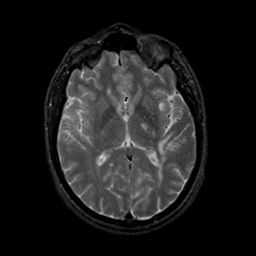

MR Study #9, April 14, 1991 -- Slice #26